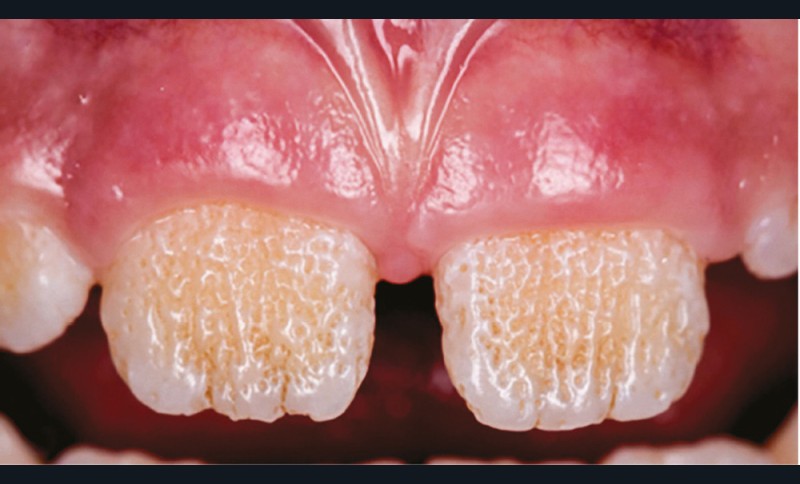

L’amélogenèse imparfaite est le nom donné à un groupe hétérogène de pathologies caractérisées par un défaut inné du développement de l’émail affectant toutes les dents des deux dentures. Ce sont des maladies génétiques dont l’origine est la mutation d’un gène impliqué dans l’amélogenèse. À ce jour, plus de 200 mutations différentes ont été identifiées, ce qui explique des phénotypes très variés [1]. Selon le stade de la maladie, l’émail est hypoplasique (défaut quantitatif), hypominéralisé, ou hypomature (défauts qualitatifs) : il est fin, fragile, tâché ou dyschromique. L’intensité des défauts peut être légère (forme frustre) ou très sévère, allant jusqu’à une absence totale d’émail. Son aspect est altéré par des dyschromies, fractures ou irrégularités de surface (fig. 1-4).